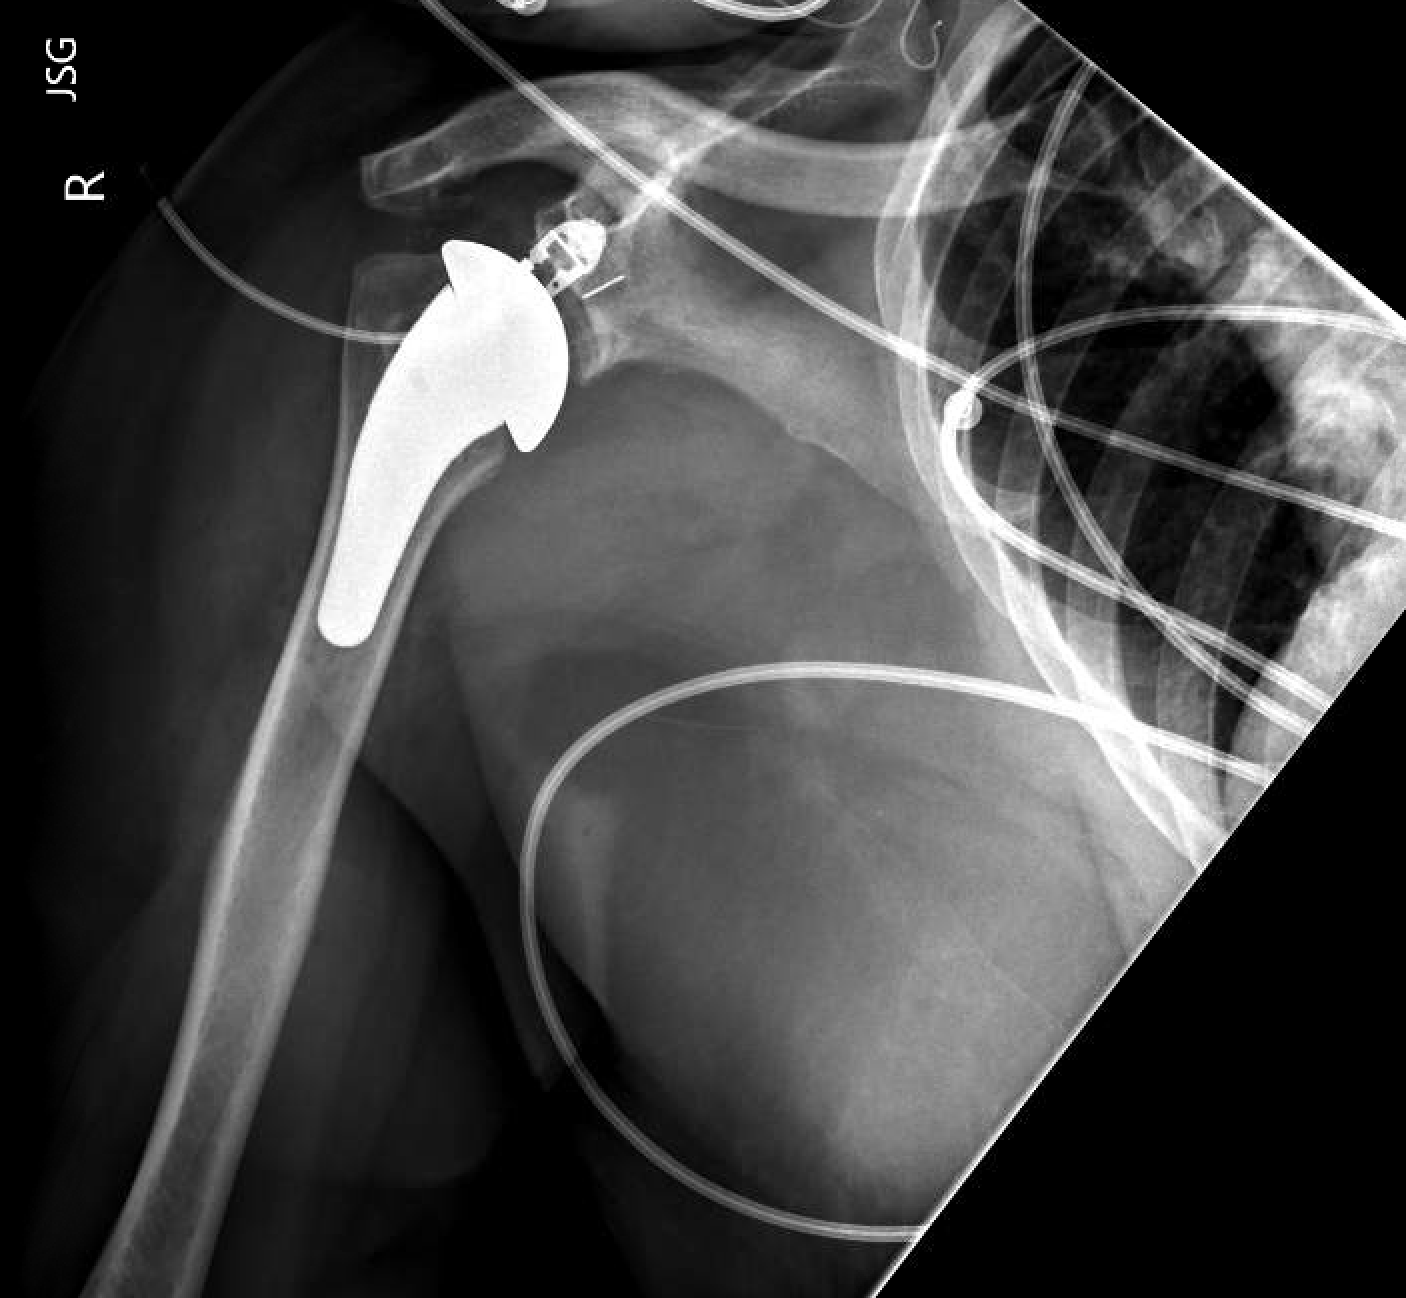

What Constitutes A Shoulder Replacement . What are the types of replacement? A shoulder replacement is a procedure that tries to eliminate the source of pain and dysfunction by replacing damaged parts of the shoulder joint with artificial components. When is a shoulder replacement needed? There are three types of shoulder replacement surgeries: The specific type of shoulder. Matthew noble walks you through what to expect during shoulder replacement. Total shoulder replacement, also known as total shoulder arthroplasty, is a procedure where portions of the bones in the shoulder joint are removed and replaced with. This is the most common type. Shoulder replacement surgery involves removing damaged areas of your shoulder and replacing them with artificial parts. In shoulder replacement surgery, the damaged parts of the shoulder are removed and replaced with artificial components, called a prosthesis. What is the anatomy of the shoulder? The procedure is performed to relieve pain and.